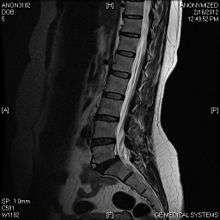

Viewed in a lateral radiograph, it appears as a triangular shaped bone fragment, not unlike an anterior lip fracture, but with softer edges.

Limbus vertebra is not always symptomatic, but severe cases may lead to more serious pathological conditions and chronic pain. In rare instances, a posterior limbus vertebra has been described causing radiculopathy due to nerve root compression.